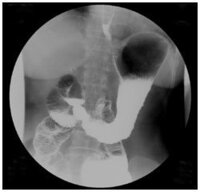

バリウム検査について 新 胃x線撮影法といわれます バリウム日記 がんの早期発見をめざして

症例 1 スキルス胃がん